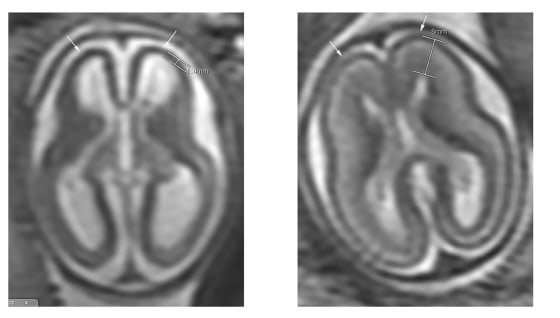

“Two areas in the adult mouse brain contain neural stem cells: the subventricular zone of the anterior forebrain and the subgranular zone of the hippocampus,” they wrote in their report.

And sure enough, Zika got into those brain regions when the mice were infected and appeared to kill some of the stem cells in there.